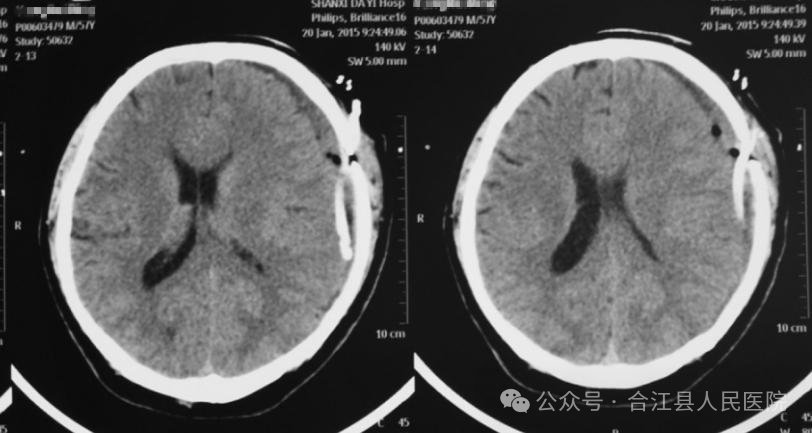

图片

慢性硬膜下血肿钻孔引流术后CT表现